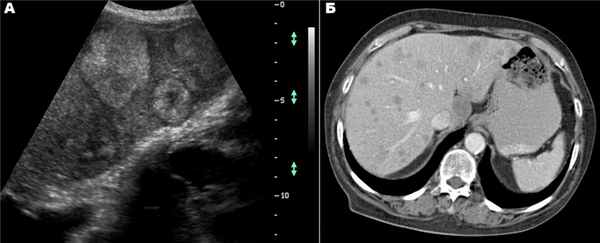

При УЗИ цистаденомы печени визуализируются в виде анэхогенных образований с внутренними перегородками. Локальные гиперэхогенные включения в пределах опухоли могут быть участками фиброза стенки, внутрикистозными кровоизлияниями или папиллярными разрастаниями. На КТ-снимках опухоль проявляется в виде очагов жидкостной плотности с локальным накоплением контрастного препарата. Часто визуализируются перегородки и пристеночные узлы. Характерными признаками цистаденом печени, отличающими их от простых кист, являются васкуляризация перегородок внутри кисты, а также наличие папиллярных разрастаний стенок [9] .

По данным УЗИ от 06.06.2013: печень увеличена, передне-задний косой размер правой доли — 189 мм; по передней поверхности правой доли печени в S4–5 лоцируется тканевое образование с неровными контурами, гетерогенной структуры, с зонами повышенной и пониженной эхогенности, размерами не менее 87 × 67 мм; желчный пузырь оттеснен описанным образованием кзади, не напряжен, стенки его уплотнены, контуры ровные, содержимое однородное, конкрементов не содержит.

На КТ органов брюшной полости от 21.06.2013 в S4–5 и умеренно в S6 определено образование с четкими неровными контурами, неоднородной структуры, которое распространялось за границы печени до передней брюшной стенки, оттесняя желудок, двенадцатиперстную кишку, желчный пузырь. Размеры образования — 115 × 75 × 124 мм. Плотность нативно +18–45 HU, в артериальную фазу плотность образования неоднородно повышалась до +115 HU, в венозную — до +100 HU, в отсроченную фазу она составляла +45–60 HU. В S2 определялся гиподенсный очаг (+50–55 HU), визуализировавшийся в венозную фазу, размером 9 мм.